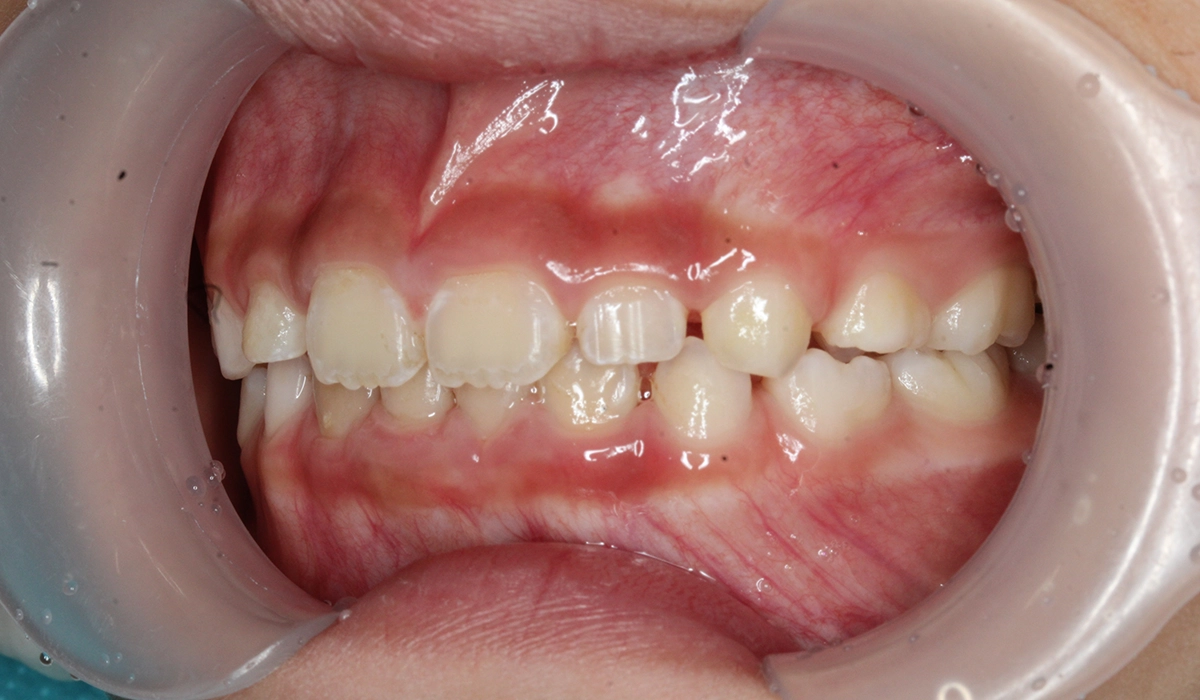

術前:正面

術後:正面